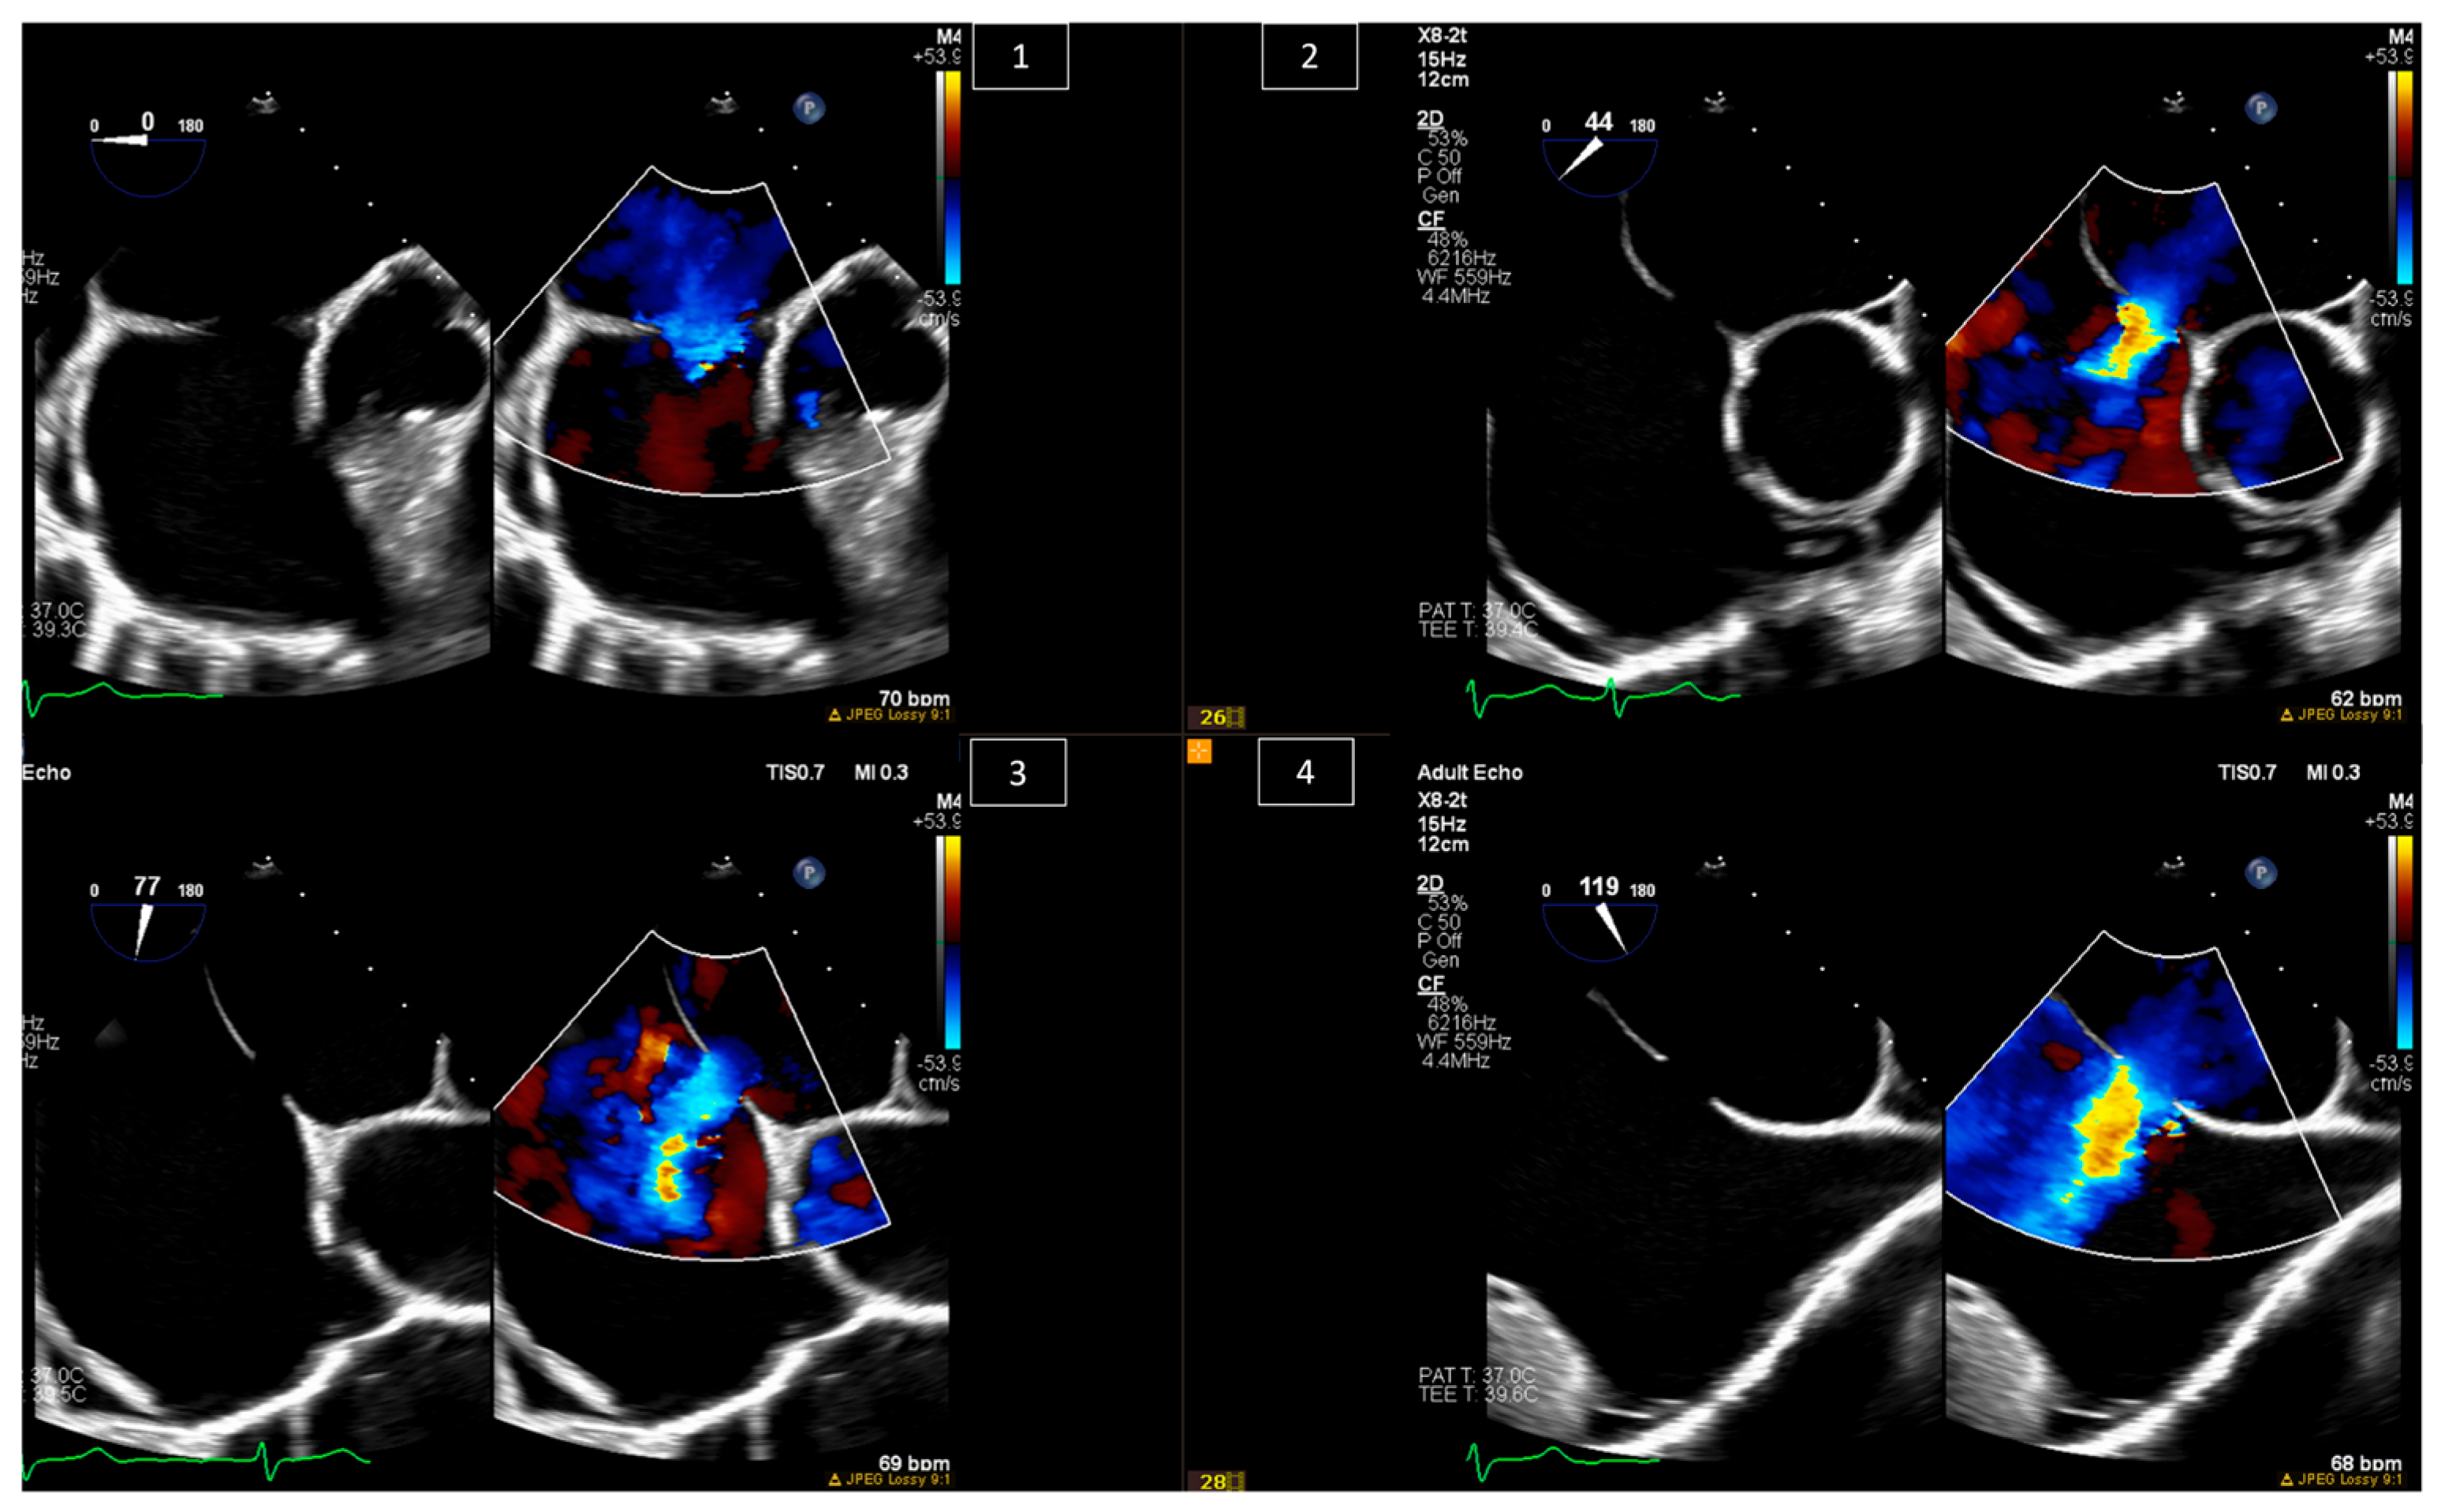

6. Baffle Complications in Atrial Switch Operations

7. Interventions in Fontan Circulation